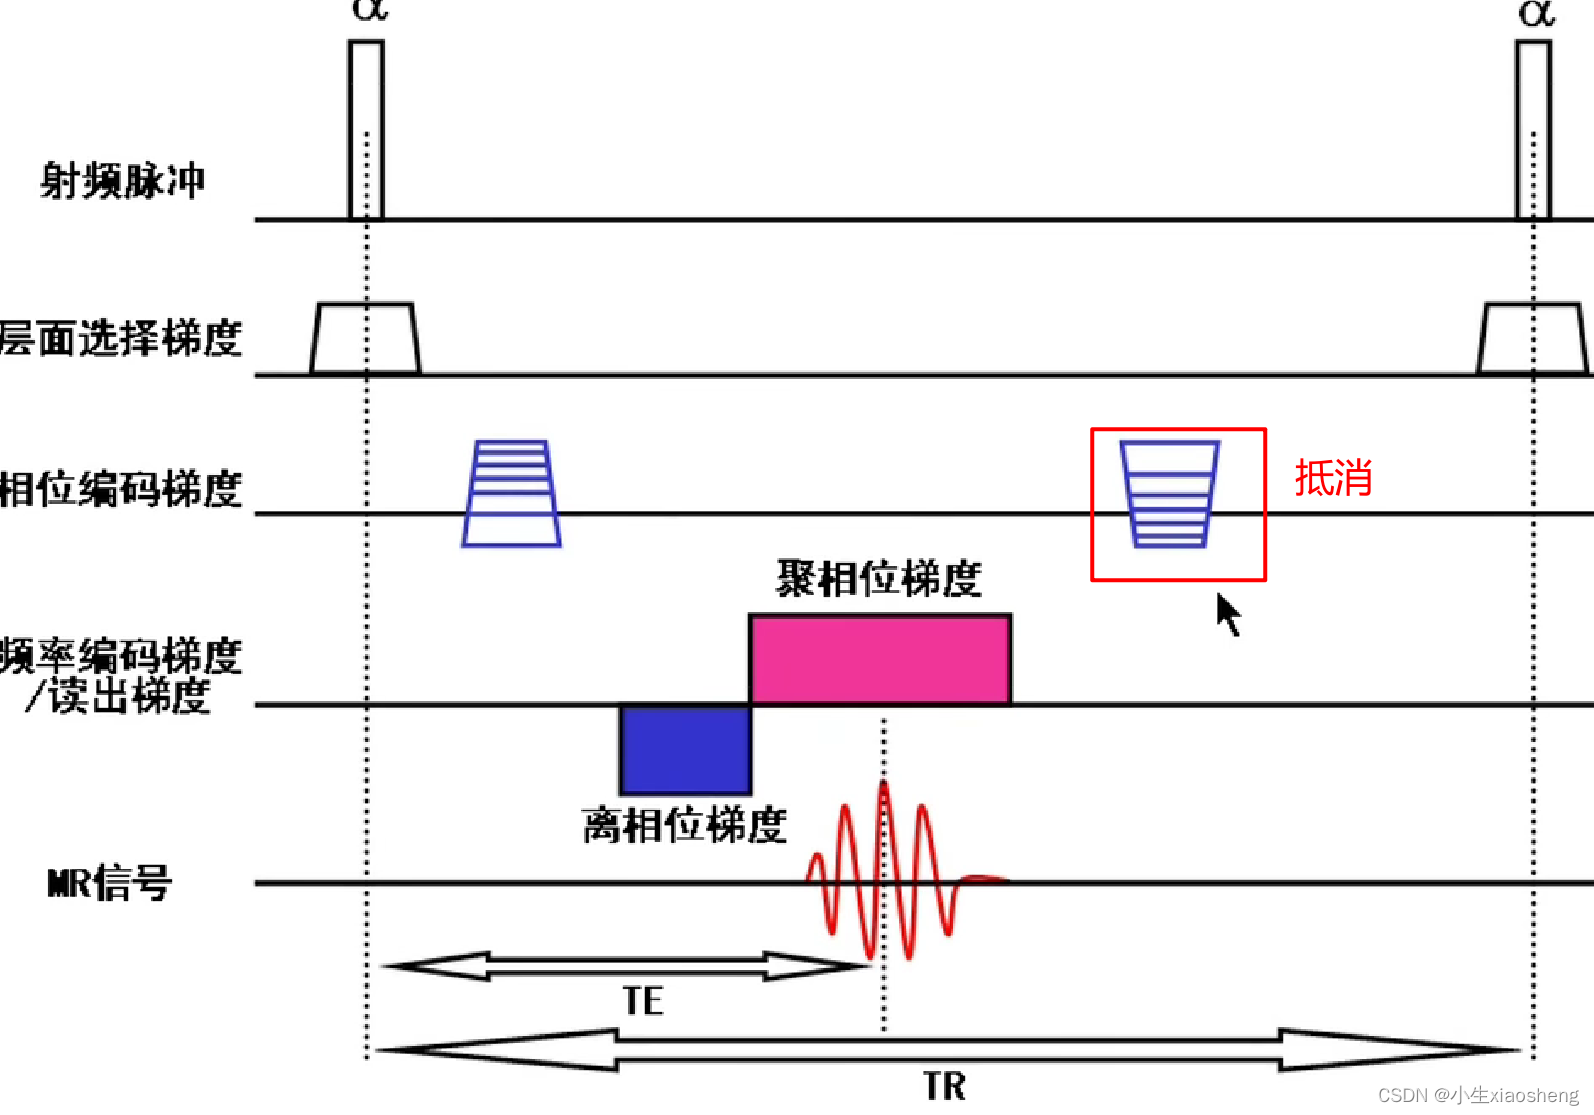

2.普通SSFP序列

梯度场抵消:SSFP序列的一个显著特点是,在Gx、Gy、Gz三个方向梯度场的正反切换完全抵消。这种抵消作用使得流动的信号得到补偿,从而在图像中减少或消除流动伪影。